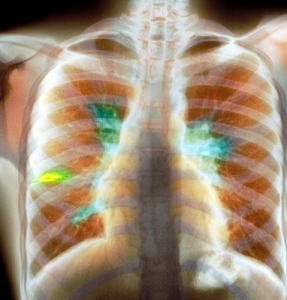

Бронхоаденит туберкулёзный, описание симптомов болезни, профилактика, причины, последствия болезни и ее лечение

Возбудитель туберкулеза (туберкулезная палочка, палочка Коха) при первом попадании в организм может поразить не только легкие, при бронхоадените бактерия проникает в лимфатические узлы, расположенные рядом с трахеей, крупными бронхами и поражает их.